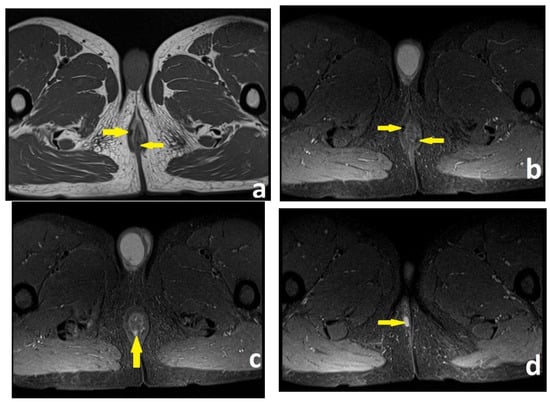

The 3D-EAUS was performed by a colorectal surgeon certified in endoanal imaging with 10 years of experience who was blinded to the results of the MRI. A colorectal surgeon trainee in endoanal imaging participated in the 3D-EAUS procedure. Hydrogen peroxide enhancement was not applied. A perianal fistula was recognized as a hypoechoic tract that penetrated the anal sphincters or the perianal anatomical spaces and could branch into secondary extensions. The internal orifice of the fistula was shown to disrupt the IAS, according to Cho’s three criteria [11]. A perianal abscess was visualized as a mixed hypo- and hyperechoic region with debris and gas bubbles (Figure 3 and Figure 4).

Figure 3. Patient no. 1; preoperative 3D-EAUS. (a) Axial plane. Intersphincteric perianal fistula with an internal opening at the posterior wall (5 o’clock) of the anal canal (yellow circle), according to Cho’s criterion I [11]. Internal anal sphincter, visualized as a black, hypoechoic ring (green arrow). External anal sphincter, visualized as a bright, hyperechoic circular structure (orange arrow). (b) Sagittal plane, tridimensional reconstruction. Intersphincteric perianal fistula with an internal opening at the posterior wall (5 o’clock) of the anal canal at a depth of 17 mm from the anal verge (yellow circle). Internal anal sphincter, visualized as two black, hypoechoic lines (green arrows). External anal sphincter, visualized as a bright, hyperechoic circular structure (orange arrows).